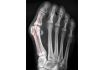

L'hallux valgus, appelé aussi « oignon » au pied, est une déviation anormale du gros orteil vers le deuxième orteil (c'est à dire vers l'extérieur).

L'os appelé premier métatarsien se déplace à l'opposé du gros orteil, vers l'intérieur du pied et l'articulation entre le métatarsien et la première phalange du gros orteil (articulation métatarso-phalangienne) devient très saillante, formant une bosse sur le bord interne de l'avant pied, d'où le nom d'« oignon ».

LES DIFFÉRENTS STADES DE L'HALLUX VALGUS

La sévérité de l'hallux valgus dépend de l'angle de la déviation et de l'importance des autres atteintes du pied.

L'hallux valgus léger

La déviation est inférieure à 20°.

La phalange du gros orteil et le métatarse sont encore correctement emboîtés.

L'hallux valgus modéré

La déviation se situe entre 20° et 40°.

Le gros orteil tourne vers l'extérieur du pied, la phalange est déplacée par rapport au métatarse et ne s'emboîte plus correctement.

Le gros orteil entre en conflit avec le second orteil.

L'hallux valgus sévère

L'angle de la déviation est supérieur à 40°.

Le gros orteil passe au-dessous ou au-dessus du deuxième orteil.

L'arthrose accentue la déviation, jusqu'à provoquer une luxation complète de l'articulation du gros orteil qui perd ainsi sa fonctionnalité.